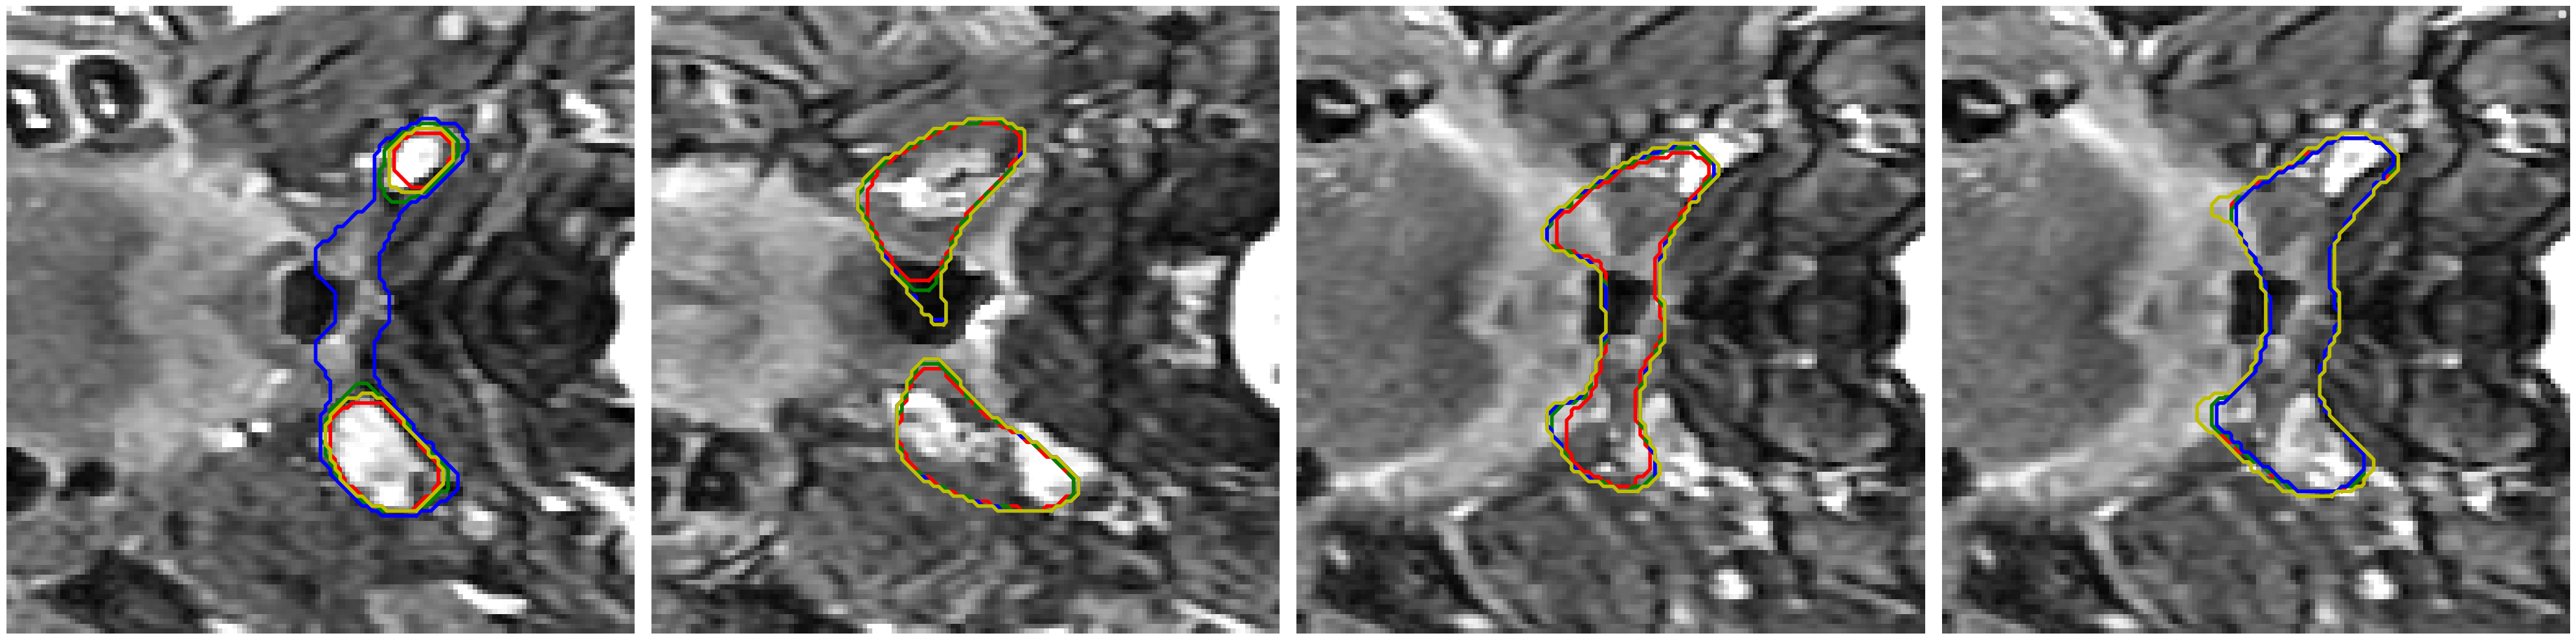

Visual comparison of segmentation results.

We provide visual comparisons of the segmentation results of all methods on the NPC dataset in Fig. 9 and Fig. 10, where different colors indicate the segmentation is obtained by different expert annotators. The segmentation results of ProSeg are more diverse and personalized than those of other methods. The segmentation results of ProSeg are more consistent with the ground truth while maintaining diversity among the generated segmentations. The results demonstrate that ProSeg effectively captures expert-specific characteristics and generates diverse segmentation results. For some methods, the segmentation from all the experts is the same, which means the diversity is poor. In Fig. 6(b), the second row shows the segmentation from our ProSeg, the third row shows the segmentation from the DPersona (stage 1) and the fourth row shows the segmentation from the DPersona (stage 2). For the second image, in the gold standard, three experts give segmentation containing two separate parts. Our ProSeg captures the character, while other models can hardly capture this difference, and generation methods can not tell which expert gives the two-part segmentation as shown in the figure that the color of the two-part segmentation is different from the Gold standard.